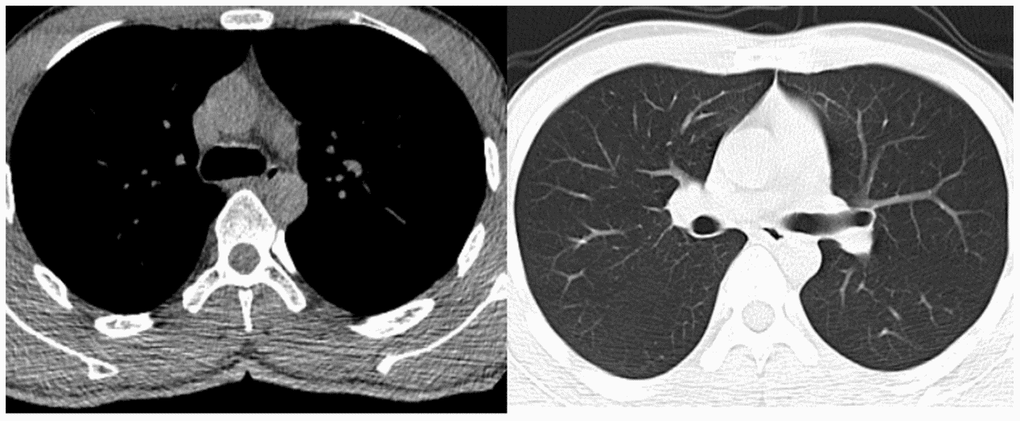

A 52-year-old male suffering with a L3 LBF presented with lower back pain and serious weakness in both lower limbs. The patient had history of shopping while wearing an ordinary mask. Physical examination indicated that his bilateral hallux dorsal extensor muscle strength level was 2, bilateral tibialis anterior muscle strength was level 2, bilateral quadriceps muscle strength was level 4, and bilateral iliopsoas muscle strength was level. X-ray, magnetic resonance imaging (MRI), and computed tomography (CT) examinations revealed an L3 LBF as well as severe spinal cord compression (Figure 1). The patient denied experiencing fever, cough, sputum production, dyspnea, nausea or vomiting. There was no significant lung abnormality on preoperative CT examination (Figure 2), and tests for viruses indicated the patient to be influenza a virus RNA (-), influenza b virus RNA (-), and respiratory syncytial virus RNA (-). Routine blood counts showed leucocytes 11.43 g/L, erythrocytes 4.87 g/L, hemoglobin 139 g/L, platelets 208 g/L, neutrophils 88.5%, lymphocytes 5.9%, monocytes 5.5%, eosinophils 0%, and basophils 0.1%.

Figure 2. Preoperative chest CT examination of the patient.